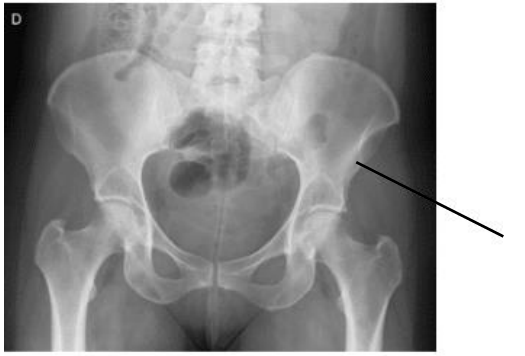

No exame abaixo podemos visualizar um detalhe anatômico ósseo denominado:

A imagem radiológica abaixo aponta pela seta a estrutura anatômica denominada: